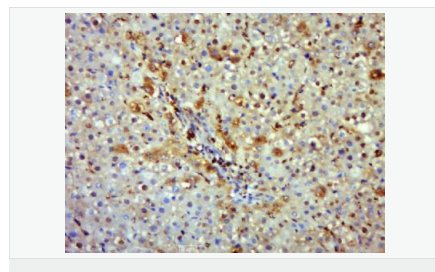

交叉反應(yīng):Human,Mouse,Rat(predicted:Dog,Pig,Horse,Sheep) 推薦應(yīng)用:WB,IHC-P,IHC-F,ICC,IF,Flow-Cyt

| 產(chǎn)品應(yīng)用 | WB=1:500-2000 IHC-P=1:100-500 IHC-F=1:100-500 Flow-Cyt=1μg/Test ICC=1:100-500 IF=1:100-500 (石蠟切片需做抗原修復(fù)) not yet tested in other applications. optimal dilutions/concentrations should be determined by the end user. |